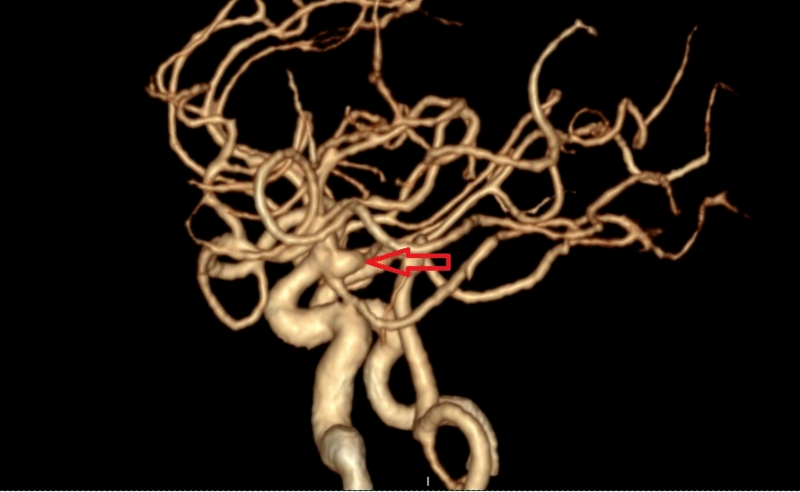

將患者收入神經(jīng)外科病房后,值班醫(yī)生詳細(xì)詢問了兩位病人的發(fā)病情況,仔細(xì)地做了體格檢查并閱讀了患者的頭部CTA,考慮他們的動脈瘤已經(jīng)破裂,如果再次破裂,后果極其嚴(yán)重,死亡率接近50%!為此,患者入院后,急診醫(yī)學(xué)科緊急聯(lián)系導(dǎo)管室,開啟 急診腦卒中綠色通道,在完善了腦血管造影術(shù)后(Digital subtraction angiography,DSA),兩位患者顱內(nèi)的動脈瘤及全部腦血管情況均已清楚地顯示了出來。

黃小山詳細(xì)地與患者家屬解釋了疾病情況及手術(shù)方案、風(fēng)險,患者家屬表示理解,并對醫(yī)院的技術(shù)能力及設(shè)備非常信任,愿意在博羅分院進(jìn)行手術(shù)治療。緊急完善術(shù)前準(zhǔn)備后,在神經(jīng)外科主任醫(yī)師羅洪海的指導(dǎo)下,主任醫(yī)師晏廣及主任醫(yī)師黃小山順利地完成了患者歐某的動脈瘤的栓塞。術(shù)后復(fù)查造影,顯示患者動脈瘤栓塞滿意,造影已無動脈瘤顯影,且載瘤動脈均保持通暢,“炸彈”順利拆除。另一位患者李某因動脈瘤寬頸,胚胎型大腦后動脈,考慮開顱夾閉合適,由黃小山帶領(lǐng)曹繁明對患者施行開顱動脈瘤夾閉處理。